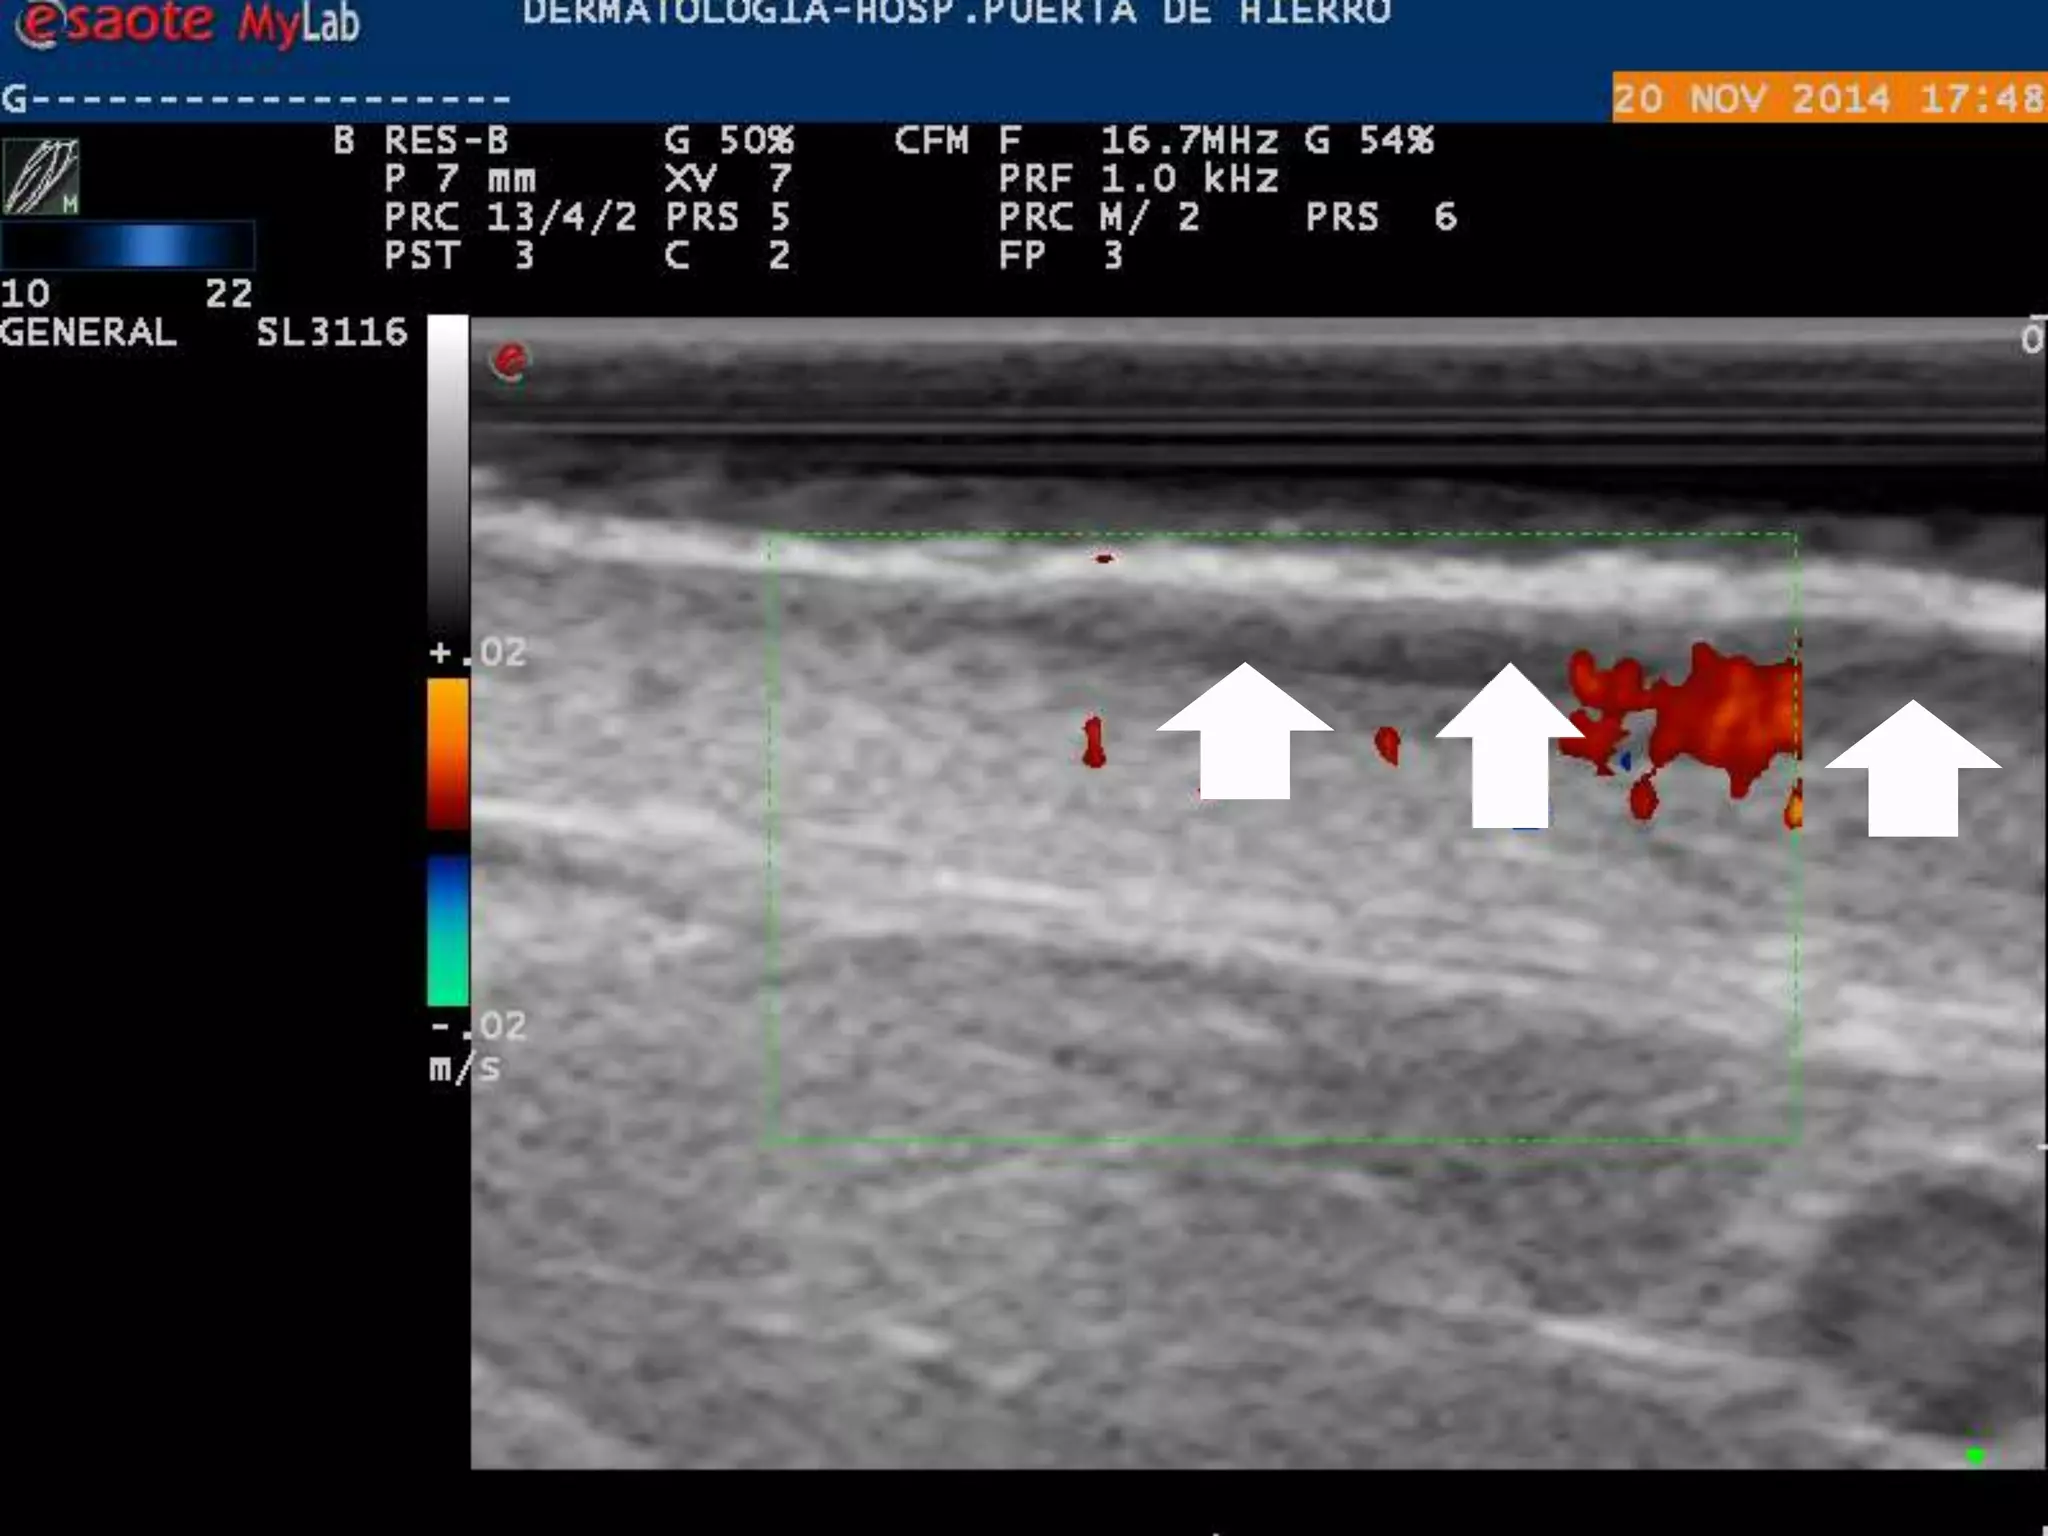

2)El flujo Doppler Suele estar aumentado=

Aumento de flujo sanguíneo

INFLAMADO

LOCALIZACION DE INFLAMACION

DERMIS

ROSACEA